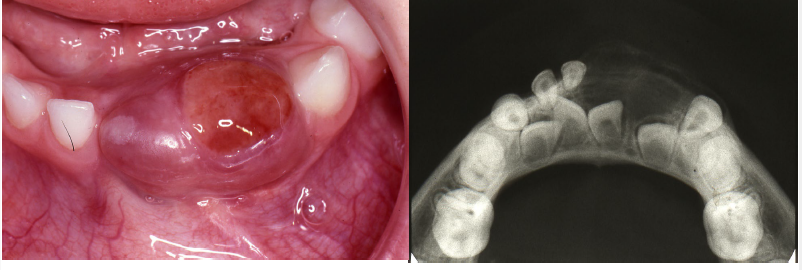

central giant cell granuloma occlusal radiograph of mandible

may demonstrate CGCG as cause of expansion of internal and external cortical bones

central giant cell granuloma maxillary occlusal radiograph

demonstrates CGCG as cause of divergence of roots of maxillary central incisors